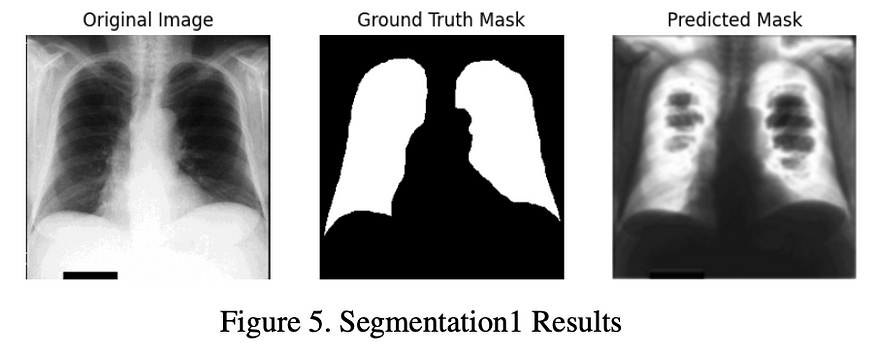

七、任务 5:从胸部 X 射线图像中分割肺区域

7.1. 数据加载和预处理:

该代码有效地处理了胸部 X 射线图像及其相应肺区域掩模的加载和预处理。实施了强大的路径格式,以确保跨平台兼容性,这对于协作项目至关重要。将图像大小适当调整为一致 (256, 256) 像素尺寸,并归一化为 [0, 1] 范围内的值。这种标准化是深度学习图像预处理的常见做法。

7.2. 模型架构:

该代码实现了 U-Net 架构,这是医学图像分割任务中一种成熟且广泛使用的方法。该模型由编码器和解码器组成,具有跳跃连接,以保留整个网络的空间信息。对卷积层使用“relu”激活,对最终输出层使用“sigmoid”激活,符合二进制分割问题的最佳实践。

7.3. 训练:

模型训练过程经过适当配置,包括优化器(Adam)和损失函数(二元交叉熵)的选择。训练循环运行 10 个 epoch,批次大小为 16,其中 20% 的数据被分配用于验证,确保在训练时间和模型性能之间进行合理的权衡。

7.4. 测试和可视化:

该代码演示了模型对测试数据集进行预测的能力。可视化是模型评估的重要组成部分,我的方法有效地利用 Matplotlib 在地面实况掩码和预测掩码旁边显示随机测试图像。

实现的肺区域分割模型在测试数据集上的准确率为 0.70。虽然该模型在识别胸部 X 射线图像中的肺部区域方面提供了相当高的准确性,但值得注意的是,预测的掩模在肺部区域内似乎是浅灰色的,这表明在准确描绘肺边界方面还有进一步改进的余地。为了解决这个问题,考虑了几种策略,包括使用更复杂的U-Net架构进行体验,应用数据增强技术,使用加权损失函数来解决类不平衡问题,实现学习速率调度,以及探索后处理方法。这些努力旨在提高模型的分割精度,并确保更精确地识别胸部 X 射线图像中的肺部区域。需要进一步的优化和微调,以达到肺区域分割所需的准确性水平。

7.5. 改进建议:

为了进一步增强模型的泛化性,请考虑实施数据增强技术,例如旋转、翻转和亮度调整。这些技术可以提高对看不见的数据的性能。在训练过程中保存模型检查点的合并机制。这种做法可确保不会丢失宝贵的训练进度,从而轻松恢复模型或进行微调。在医学图像分析的背景下,使用适当的指标(如骰子系数、灵敏度、特异性和 ROC AUC)评估模型至关重要。这些指标提供了对模型性能的全面评估。如果数据集中存在类不平衡,则解决类不平衡问题至关重要。探索加权损失函数或数据重采样等技术,以减轻类不平衡对训练的影响。